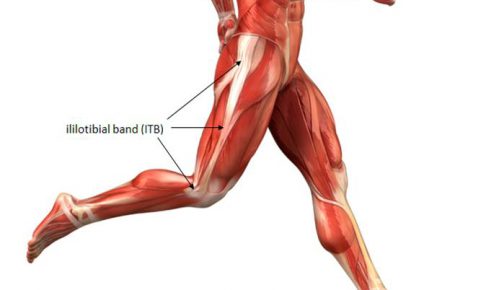

もも横の靭帯

こんばんは!横浜本牧パーソナルトレーナー宮原崇です。 確定申告を目前に大量なる資料整理に日々追われているので、時間という貴重な資源をどのように使うかが常に課題となっています。 さて、ひざの外側に痛みが発している時に、フィ…